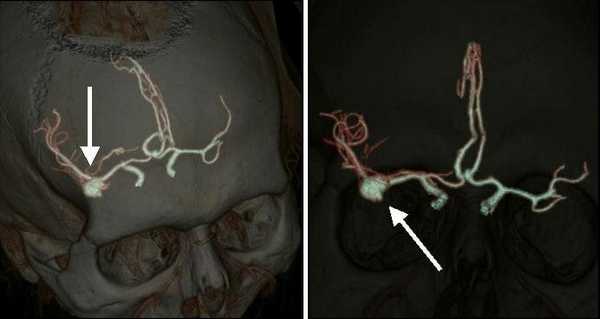

У больной с АА бифуркации БА (рис. 3) ВЭСА позволила уточнить локализацию шейки АА и контралатеральных задней мозговой и верхней мозжечковой артерий, после чего стало возможным клипирование АА без риска нарушения кровотока по указанным сосудам (рис. 4).

Рис. 3. Левосторонняя вертебральная ангиограмма, боковая проекция с разворотом больной П., 50 лет: АА бифуркации БА. 1 — базилярная артерия, 2 — аневризма бифуркации базилярной артерии, 3 — спинка турецкого седла.

Рис. 4. Клипирование аневризмы бифуркации базилярной артерии больной П., 50 лет. а — правосторонняя птериональная краниотомия, доступ через ретрокаротидный промежуток (вид через микроскоп); б — вид через эндоскоп с тубусом 30° через ретрокаротидный промежуток. 1 — базилярная артерия, 2 — задняя мозговая артерия, 3 — шейка аневризмы (обозначена пунктиром), 4 — шпатель на базальной поверхности лобной доли мозга, 5 — шпатель на медиальной поверхности височной доли мозга, 6 — контралатеральная задняя мозговая артерия, 7 — контралатеральный глазодвигательный нерв.